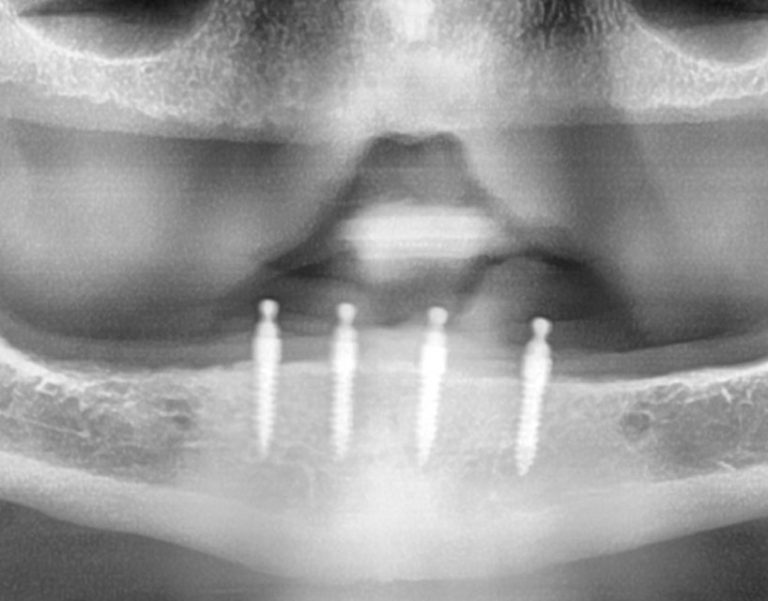

Protesis total sobre implantes